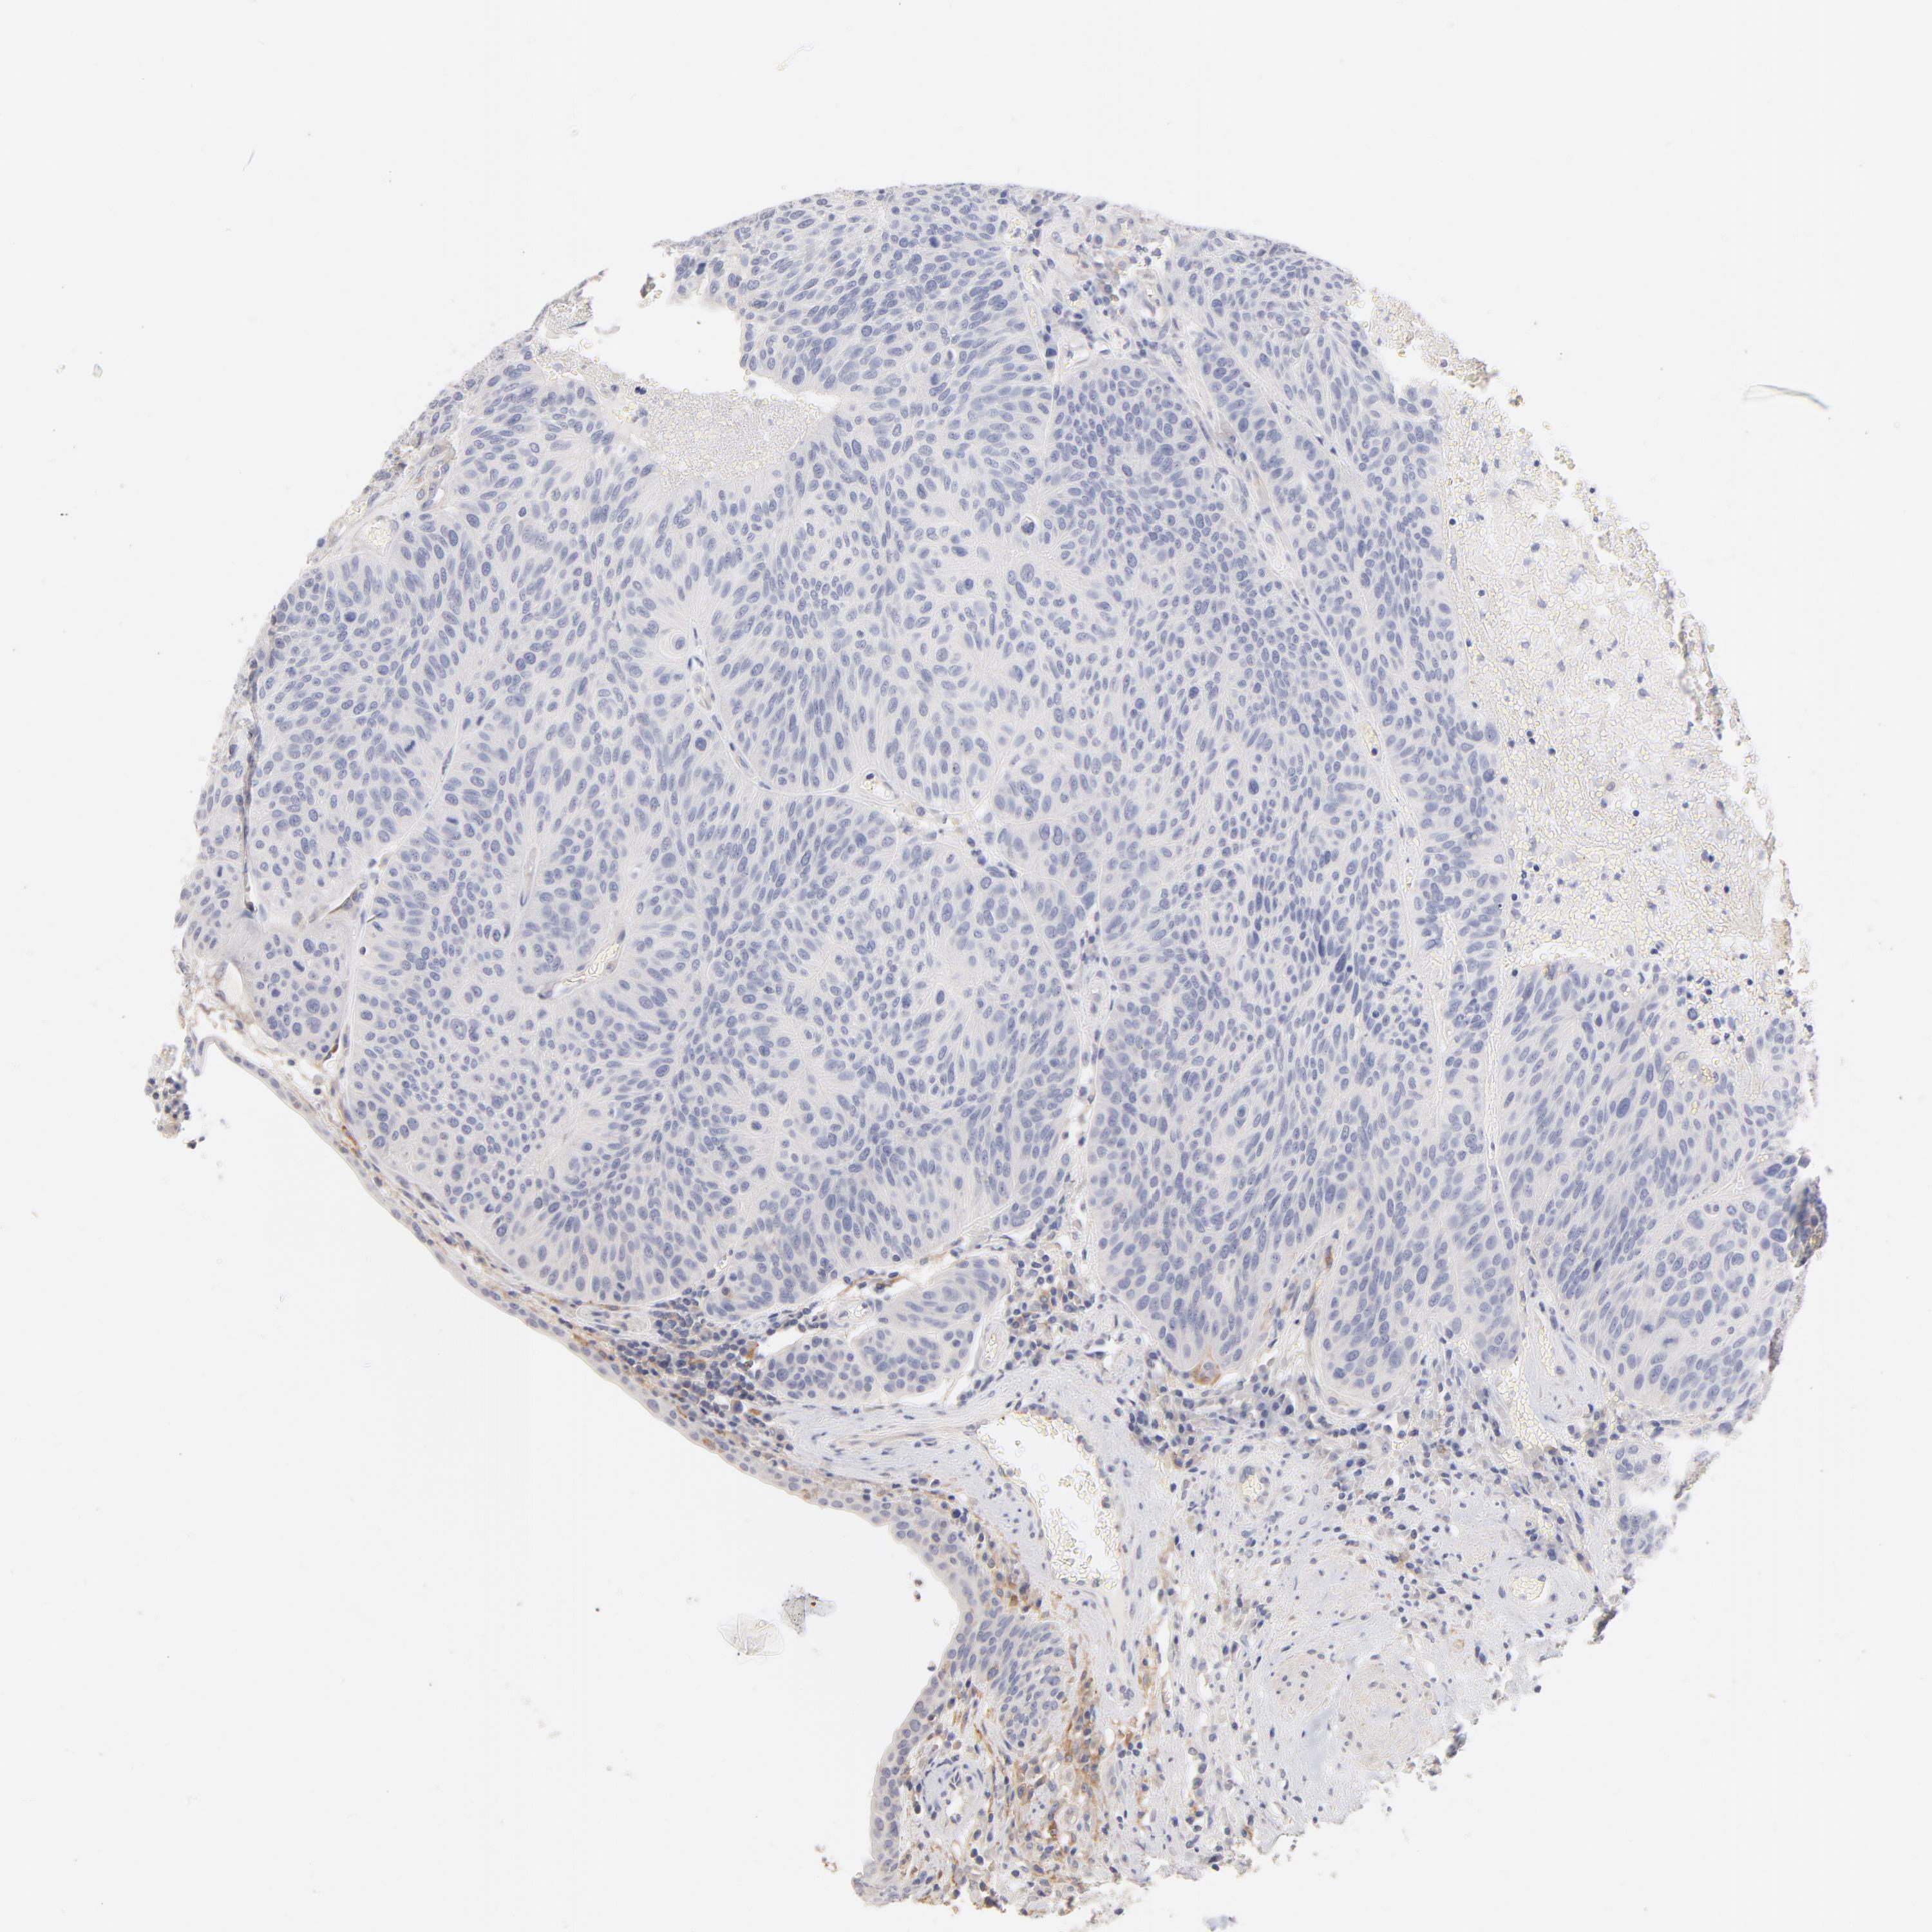

UROTHELIAL CANCER - Protein expressioni

A mouse-over function shows sample information and annotation data. Click on an image to view it in a full screen mode. Samples can be filtered based on level of antibody staining by selecting one or several of the following categories: high, medium, low and not detected. The assay and annotation is described here.

Note that samples used for immunohistochemistry by the Human Protein Atlas do not correspond to samples in the TCGA dataset.

Antibody stainingi

Antibody staining in the annotated cell types in the current human tissue is reported as not detected, low, medium, or high, based on conventional immunohistochemistry profiling in selected tissues. This score is based on the combination of the staining intensity and fraction of stained cells.

Each image is clickable and will lead to virtual microscopy that enables deeper exploration of all samples and also displays staining intensity scores, fraction scores and subcellular localization as well as patient and tissue information for each sample.

Antibody HPA003432

Staining

High

Medium

Low

Not detected

Intensity

Strong

Moderate

Weak

Negative

Quantity

>75%

75%-25%

<25%

None

Location

Nuclear

Cytoplasmic/membranous

Cytoplasmic/membranous,nuclear

Urothelial carcinoma, High grade

Urothelial carcinoma, Low grade